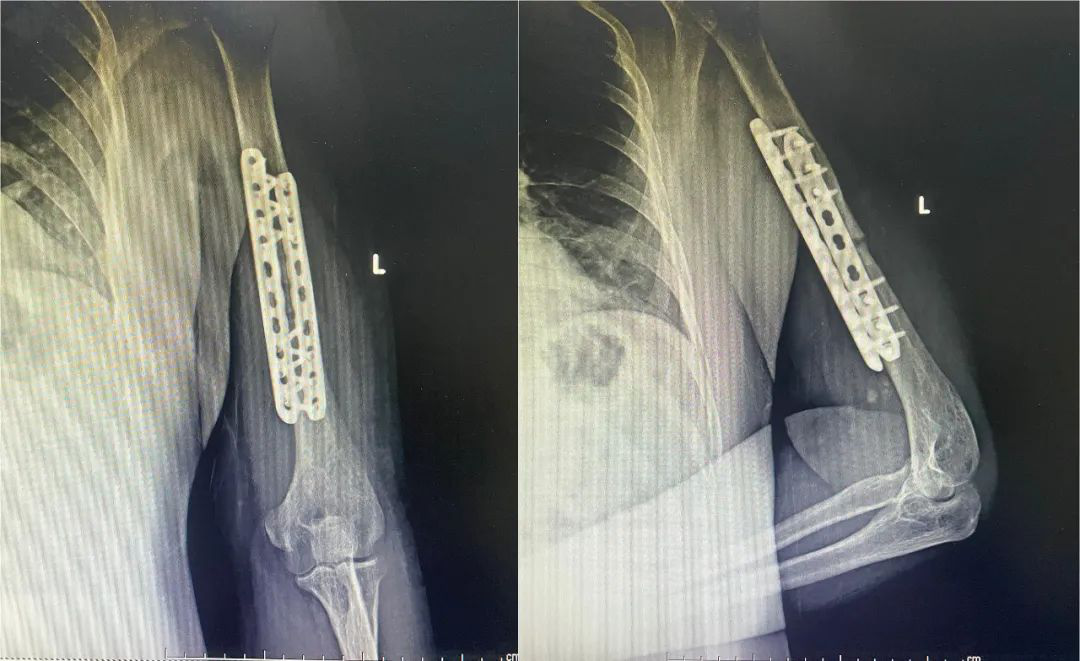

钢板固定

图片